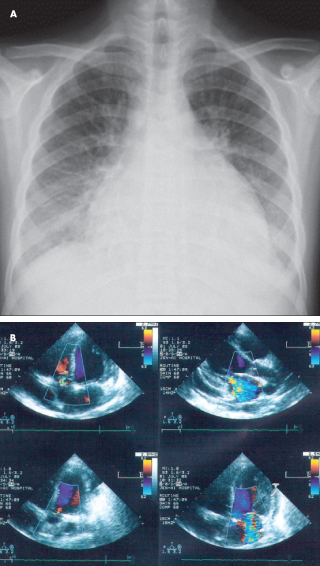

An ECG shows sinus tachycardia, with a heart rate of 130 beats per minute. A chest film on admission reveals cardiomegaly with pericardial effusion (A). Echocardiography confirms the cardiomegaly with compromised systolic function (left ventricular ejection fraction of 43.4%), massive pericardial effusion (greater than 10 mm), and moderate to severe mitral regurgitation with pulmonary hypertension (37.9 mm Hg) (B). The patient is treated with high-dose intravenous corticosteroids; however, her symptoms progressively worsen.